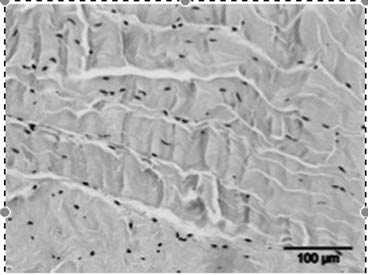

• Het stimuleren van de collageenproductie en het afvoeren van beschadigd collageen, wat resulteert in een verhoogde matrix-turnover.